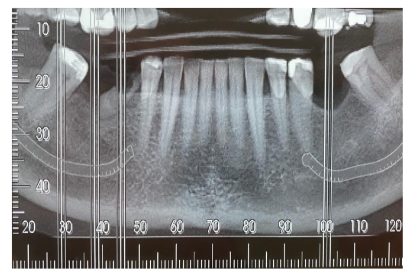

Paciente de 47 anos de idade, normossistêmico, apresenta indicação de extração do dente 45 e reabilitação por implantes dos dentes 36, 45 e 46. De acordo com a imagem abaixo, constatou-se que: a distância do nervo alveolar inferior em relação à borda alveolar é de 10mm na região do dente 45, 12mm na região do dente 46 e 13mm na região do dente 36. Além disso, a distância entre o dentes 47 e 44 é de 17mm e entre os dentes 37 e 35 é de 10mm.